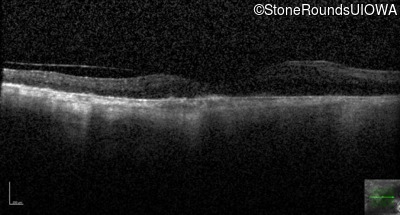

Type 1 Usher Syndrome (IB1a)

Age at visit: 62 years

This 62 year old man has had profound hearing loss since birth and has communicated using sign language for his entire life. He first noticed a problem with his vision at about age 11 when he noticed night blindness and began to trip over objects that he should have seen.